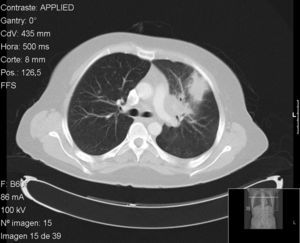

Caso 1: mujer de 41 años diagnosticada de espondilitis anquilosante, HLA-B27 positivo a los 30 años de edad, con afectación axial y uveítis anterior aguda recidivante. Ante insuficiente respuesta a AINE, se inició tratamiento con adalimumab en 2006, previo cribado de TB (en el momento del Mantoux solo estaba recibiendo tratamiento con AINE). Habiendo recibido 35 meses de tratamiento con adalimumab, en 2009 la paciente presentó un cuadro de fiebre, tos seca, malestar general, odinofagia y cefalea. Se realizó una TC pulmonar que mostró una masa de 4cm en segmento anterior del lóbulo superior izquierdo con adenopatías suprahiliares y prevasculares (fig. 1). El test de Mantoux en esta ocasión fue de 20mm a las 48 h. Se realizó broncofibroscopia con biopsia transbronquial, que reveló una mucosa con inflamación crónica granulomatosa con necrosis, y cultivo positivo para Mycobacterium tuberculosis (M. tuberculosis). Tras tratamiento tuberculostático con rifampicina, pirazinamida e isoniazida, la paciente quedó libre de enfermedad.